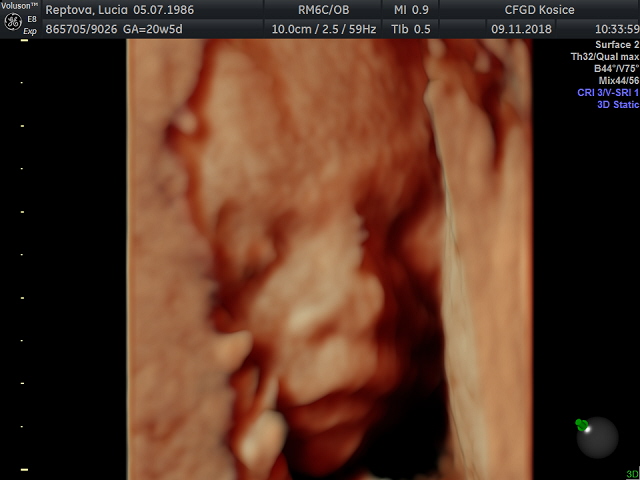

Baby mam otazocku - na lavej strane podbruska sa mi vyduva taka hrca asi ako pomaranc velka (sem tam, ale dnes v priebehu celeho dna) a je aj tvrdsia. Vobec to neboli, ani nemam krce ani nic. Len sa objavi a je tam (dnes ozaj intenzivne). No a presne v tom mieste citim ale aj posledne dva dni dost intenzivne kopkanie pocas celeho dna. Myslite ze to moze byt nas maly takto vyduty? Lebo stresujem ci aj to je tvrdnutie brucha. Deje sa to len ked sedim v kludne alebo lezim. Ked chodim tak nic.

@ivka2112 no môže to byť maternica, alebo malý ale skôr malinký keď ti tam kopká vyduva sa

@ivka2112 ano to malý sa tak hemží aj ja to tak mam normálne cítim ako sa tam uloží a ostane tak aj hodinu potom už ťa hrca nieje